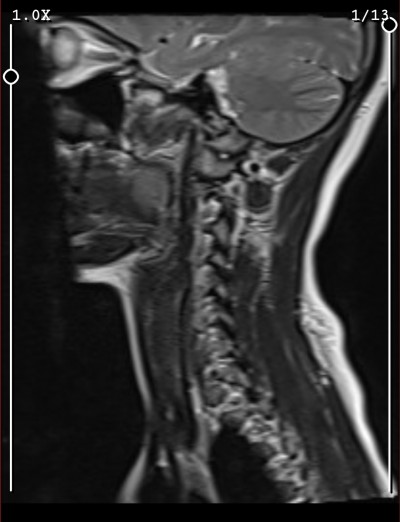

10 gündür geçmeyen Boyun ve sırt ağrım için Beyin ve Sinir Cerrahisi MR istedi Sonuç için henüz gidemiyorum doktora bir bakar mısınız anlayan biri boynumda fıtık falan var mı

Boyun duzleesmen var c şekli kaybolmuş bende de var daha bu hafta Dr gittim ilaç tedavisine başladık geçince egzersiz verecekmiş.Fitik durumu varsa farklı resimlerde tam omurlarin çekildiği ordan görülebilir en alt ve bir üst ömür arasi bu fotoda sıkışık çıkmış belkide o alanda fıtık olabilir.

Evet doktor da dedi boyun düzleşmesi var diye